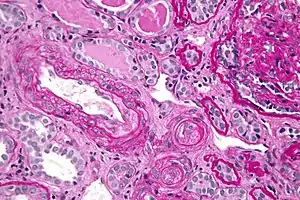

Kidney biopsy showing thrombotic microangiopathy, a histomorphologic finding seen in very high blood pressure

The pathophysiology of hypertensive emergency is not well understood. Failure of normal autoregulation and an abrupt rise in systemic vascular resistance are typical initial components of the disease process.[9]

In the kidneys, chronic hypertension has a great impact on the kidney vasculature, leading to pathologic changes in the small arteries of the kidney. Affected arteries develop endothelial dysfunction and impairment of normal vasodilation, which alter kidney autoregulation. When the kidneys' autoregulatory system is disrupted, the intraglomerular pressure starts to vary directly with the systemic arterial pressure, thus offering no protection to the kidney during blood pressure fluctuations. The renin-aldosterone-angiotensin system can be activated, leading to further vasoconstriction and damage. During a hypertensive crisis, this can lead to acute kidney ischemia, with hypoperfusion, involvement of other organs, and subsequent dysfunction. After an acute event, this endothelial dysfunction has persisted for years.[9]